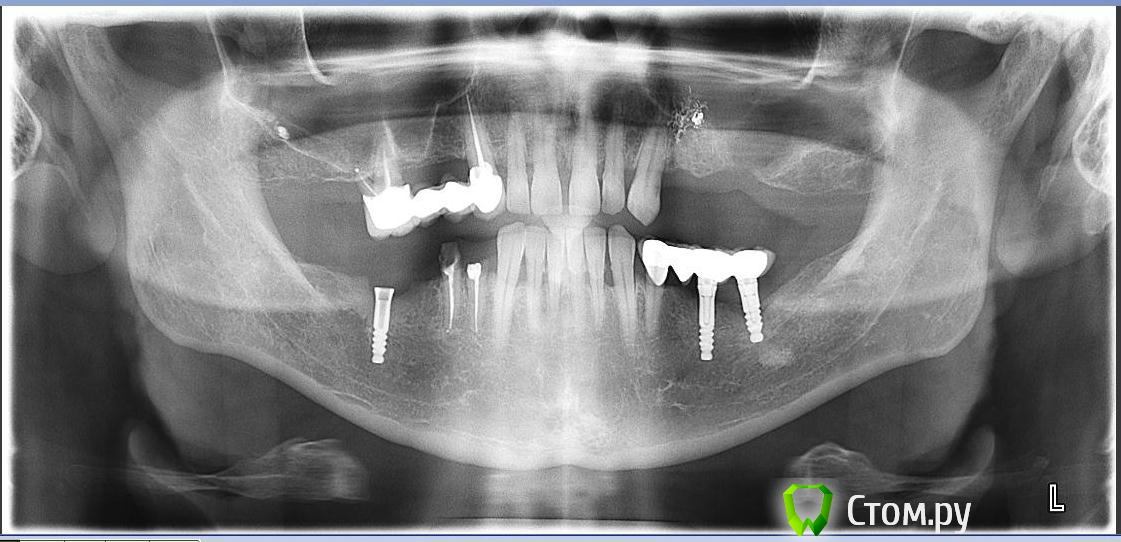

SergeiVar Опубликовано 11 июня, 2014 Поделиться Опубликовано 11 июня, 2014 Пришел пациент, вчера. Говорит что были - зубы с имплантом связаны, потом всё разболталось и выпало. Шахта импланта пустая.что за система имплатов? И что делать с имлантом 4 квадранте? Ссылка на комментарий

doc-евгений Опубликовано 20 июня, 2014 Поделиться Опубликовано 20 июня, 2014 Пришел пациент, вчера. Говорит что были - зубы с имплантом связаны, потом всё разболталось и выпало. Шахта импланта пустая.что за система имплатов? И что делать с имлантом 4 квадранте?Похоже на перевёрнутые оттискные трансферы для закрытой ложки))) Ссылка на комментарий